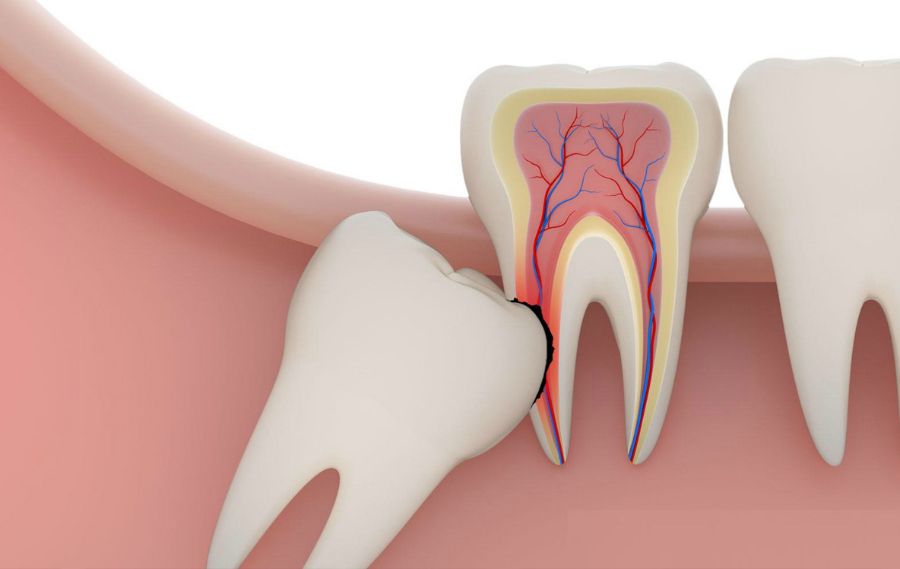

Қазіргі күнде барлық адамда 32 тіс бола бермейді. Және бұл қалыпты жағдай. Кей жағдайда адамның жақ сүйегінде бос орын болмаса да аталған ақыл тістер шығуға әрекеттенеді. Әдетті бұл жағдай 17-25 жас аралығында болады.

1. Ақыл тістер қызылиекті жарып шыға алмаса;

Мұндай жағдайда ақыл тістер адамға қолайсыздық тудырады. Тамақ жеу кезінде ауырады. Нәтижесінде қызылиекте ісік пайда болады.

2. Ақыл тісі толық өспеген жағдайда;

Жақ сүйегінің шетіне тіс щеткасының жетуі қиын. Тіс тазалағанда бұл жағдаймен күнделікті бәріміз де кездесеміз. Ал толық өспеген тіс тісжегінің ошағына айналатыны табиғи жағдай. Олар уақыт өте келе басқа сау тістерге өтеді.

3. Ақыл тістері қисық болса;

Ақыл тісі шығатындай жақ сүйегінде жеткілікті орын болмаса, шығып жатқан тістер ұдайы қозғалыста болады. Орын іздеп басқа тістерді орнынан қисайтады. Кейде тісте болатын аурулар осының салдарынан келіп шығады.